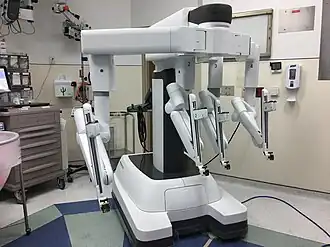

Moreover, treatment for lung cancer has been further developed with the use of robotic surgery as a method for treatment. This method involves the use of robotic arms which are manipulated by a surgeon at a console, enabling more precise movements and providing the surgeon with 3D vision of the surgical site.[47] Similar to VATS, robotic surgery has also been found to be minimally invasive and is extremely useful for removing certain parts of lung tissue that are diseased as well as surrounding lymph nodes.[48] However, comparisons of current robotic methods with VATS have shown no significant differences in patient outcome.[49]